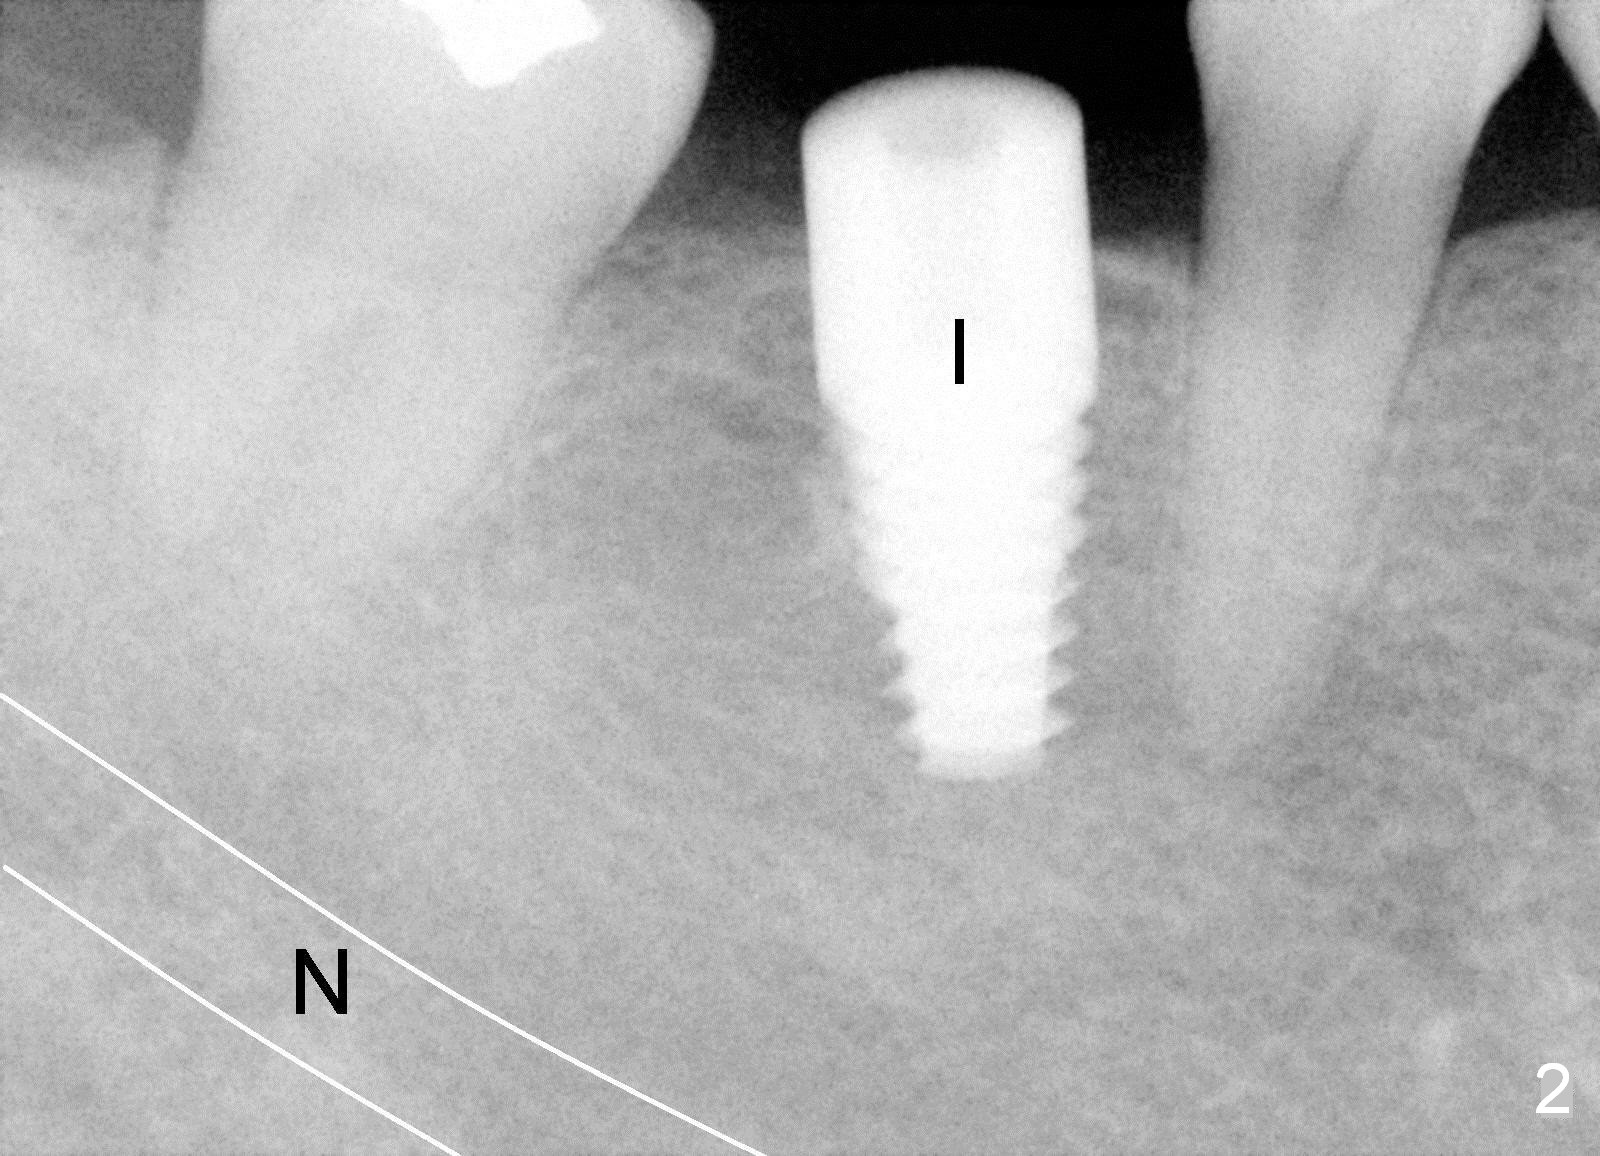

Six years ago, a 38-year-old patient presented to our office for new patient exam. She was scared of dentistry, but 3 of the third molars needed extraction. When the surgery was done painlessly, it was not too hard to persuade the patient to accept implant placement at the site of #30 (Fig.1; N: Inferior Alveolar Nerve). It was the 1st case when a 2nd implant system was adopted in the office. The implant is 3 mm shorter than the design (Fig.2). An incision was made for visibility (Fig.3). There is no bone loss 3.5 months postop (Fig.4). The crown is cemented 5 months postop (Fig.5); there is attached gingiva buccal to the implant. What surprised us the most is that she turns out to be one of the most faithful patients in our office. She never misses 6-month recall.